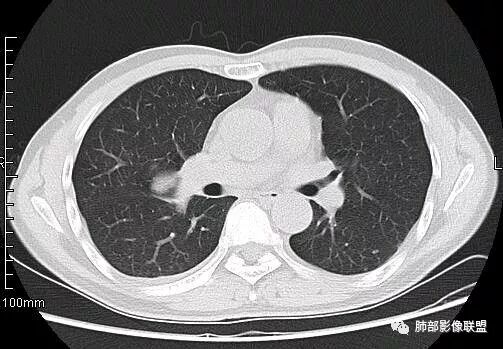

南边:从叶裂的变形,下朝上,越来越朝前扭曲,提示叶裂局部有朝前上推移的趋势

南边:下叶的支气管受压后移、变形

南边:病灶边界清,提示侵袭性弱,膨胀生长为主;这时候我们提示病灶不应该是支气管关系密切,提示间叶来源或胸膜来源

深分叶,警惕恶性

常规考虑:1、肉瘤首先考虑

2、胸膜孤立性纤维瘤待排